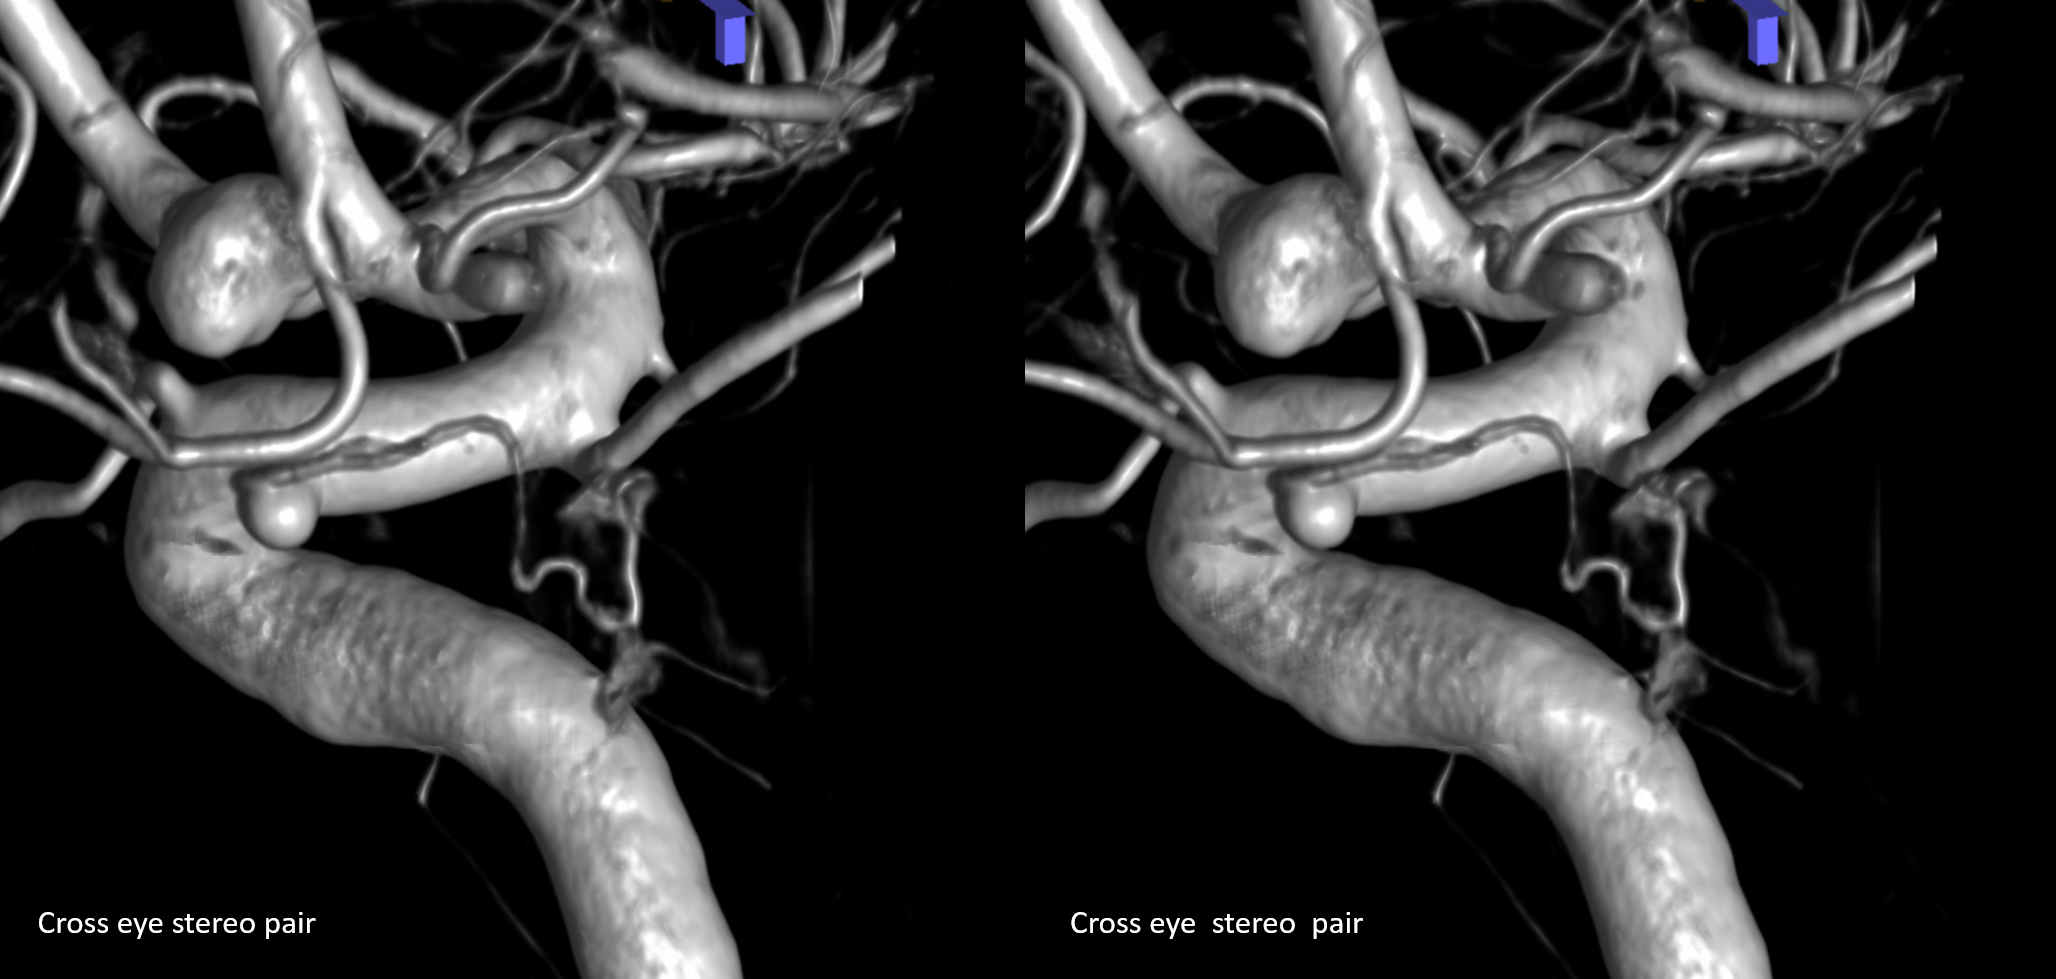

Stereos and MIPs. Both superior and inferior hypophyseals are well seen. The superior hypophyseal, despite being invisible on standard issue views, is quite large, even having two branches to the hypophysis.

Case courtesy Dr. Eytan Raz — here is a beautiful example of a very dominant superior hypophyseal artery (arrow) supplying the posterior hypophysis (arrowhead), with a correspondingly small inferior hypophyseal contribution from the MHT (dashed arrow)

Cross eye stereo

View from the back — again small inferior hypophyseal, big superior hypophyseal — balance again… See the beautiful vascular ring of the posterior pituitary — the connecting it with the contralateral side

Cross-eye stereo

Of course, there is an aneurysm here — the branch point camp would point out how this larger than usual branch is a setup for aneurysmal formation. Naturally…